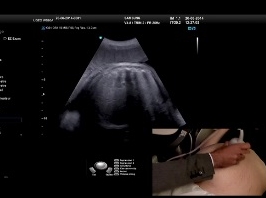

Echographie de fusion en gynécologie

• Date : 20/06/2013